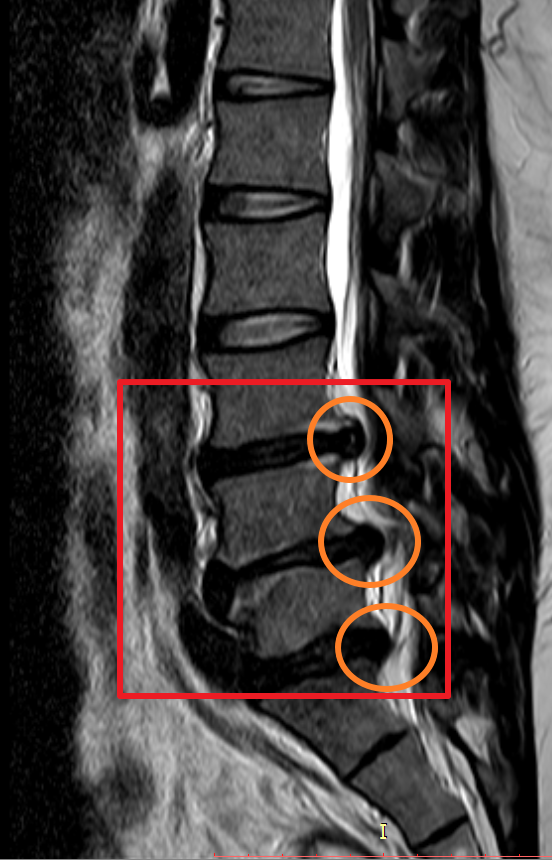

마지막으로 제가 촬영했었던 MRI 촬영 이미지를 첨부해 볼까 합니다. 이미지 순서대로 2014년, 2018년, 2020년 촬영했던 MRI 사진입니다. MRI 촬영 당시 허리디스크 상태가 좋지 않은 상황에서만 세 차례 찍었던 것이기에 이점도 고려해서 참고하시면 좋을 듯합니다.

이미지를 보시면 빨간색 네모 칸에 하얀색 기다란 세로 라인이 신경이 지나가는 부분이며 가장 바깥쪽 두꺼운 흰색 부분은 배 쪽의 지방입니다.

2018년 첫번째 허리 디스크가 첫번째 디스크가 여전히 눌려져 있으며 추가로 두번쨰 디스크가 신경을 많이 누르고 있으며 세번째 디스크는 조금씩 나오는 상황.

하지만 몸 관리를 꾸준히 잘하지 못하였고 4년 뒤 다시 허리디스크 상태가 악화하여 두 번째 MRI를 찍어보니 이전에 발병한 위치와 다른 곳에서 신경을 누르고 시작하였고 이전에 최초 발병한 허리디스크(첫 번째 동그라미)는 좀 나아졌으나 다른 곳에서(두 번째, 세 번째 동그라미) 또 문제가 생겼더군요.